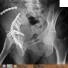

L'ortopedico mi ha prescritto gladio per rottura LCA e lesione da impatto . Io soffro di diarrea L'ho posso prendere?

buongiorno,lo può prendere limitatamente alla fase acuta e sotto copertura di gastroprotettore, ma passata la fase acuta la lesione del crociato non porta dolore. attenzione alla lesione da impatto.

Buona sera. Il Gladio è un FANS (farmaco antinfiammatorio non steroideo) e serve per lenire l’infiammazione agendo anche sul dolore. Un effetto indesiderato del farmaco può essere la diarrea e quindi in un soggetto come lei che ci soffre potrebbe aumentare il sintomo, ma come farebbero tutti i farmaci della stessa famiglia.